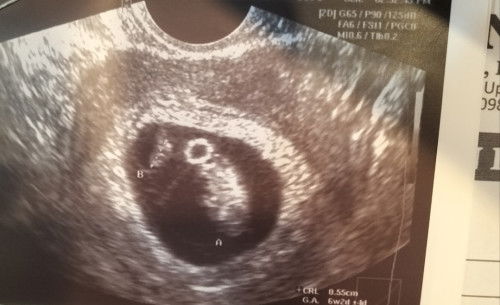

Anyone here who had monochorionic diamniotic twin?

Hello! Possible po ba na mabuhay silang dalawa kahit diagnosed no cardiac activity si baby B and 6weeks lang siya while si baby A is 8weeks na and may heartbeat? LMP is 9weeks. Thank you po sa pag sagot!